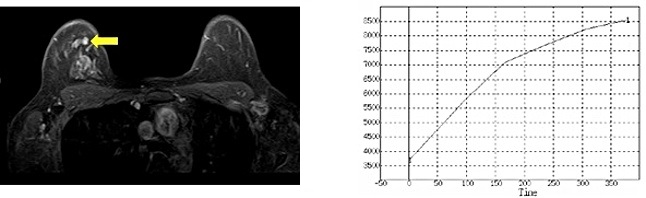

乳腺MRI検査は、乳がんの画像診断として最も感度(病変の発見率)が高い検査です。マンモグラフィー検査や超音波検査でも見えない乳がんを見つけることが報告されています。 ⇒ MRI検査